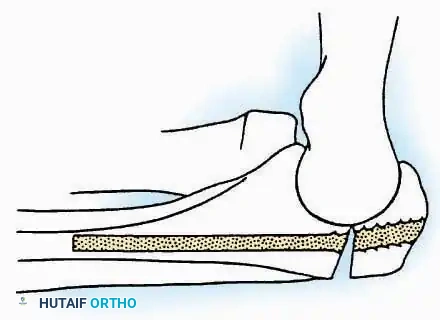

Indications: Fixation of sustentaculum tali fractures, medial process fractures, or excision of medial tarsal coalitions.

Positioning: Supine with the hip externally rotated and knee flexed (figure-of-four position).

Surgical Technique:

* Incision: Begin 2.5 cm anterior and 4 cm inferior to the medial malleolus. Carry it posteriorly along the medial surface of the foot toward the Achilles tendon.

* Superficial Dissection: Divide the fat and fascia to define the inferior margin of the abductor hallucis muscle.

* Deep Dissection: Mobilize the abductor hallucis muscle belly and retract it dorsally to expose the medial and inferomedial aspects of the calcaneal body.

* Plantar Exposure: Continue distally by dividing the plantar aponeurosis and the muscular attachments to the calcaneus, or strip them subperiosteally with an osteotome.

* Neurovascular Warning: Meticulously identify and protect the medial calcaneal nerve and the nerve to the abductor digiti minimi (first branch of the lateral plantar nerve), which are highly vulnerable during inferior retraction.